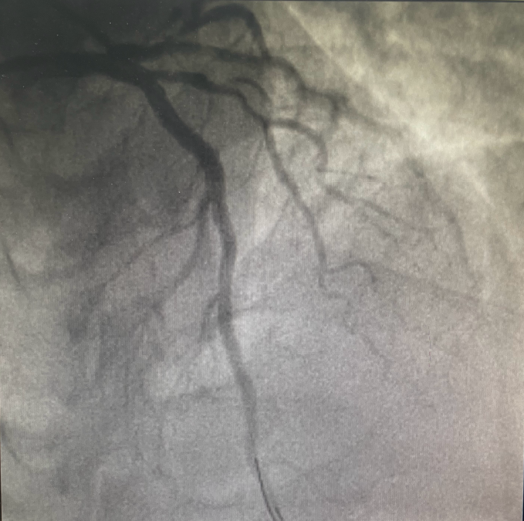

血管开通前

23:32分

血管造影显示:患者“三支血管病变”,前降支近段几乎闭塞,回旋支近段可见80%狭窄病变,右冠状动脉中段慢性闭塞。

23:38分

导丝通过病变血管,打通血管。从患者到达导管室门口至导丝通过(简称D2W),门丝时间仅用时13分钟!

23:43分

于前降支近至中段、病变处植入支架2枚,手术治疗完成。

血管开通后